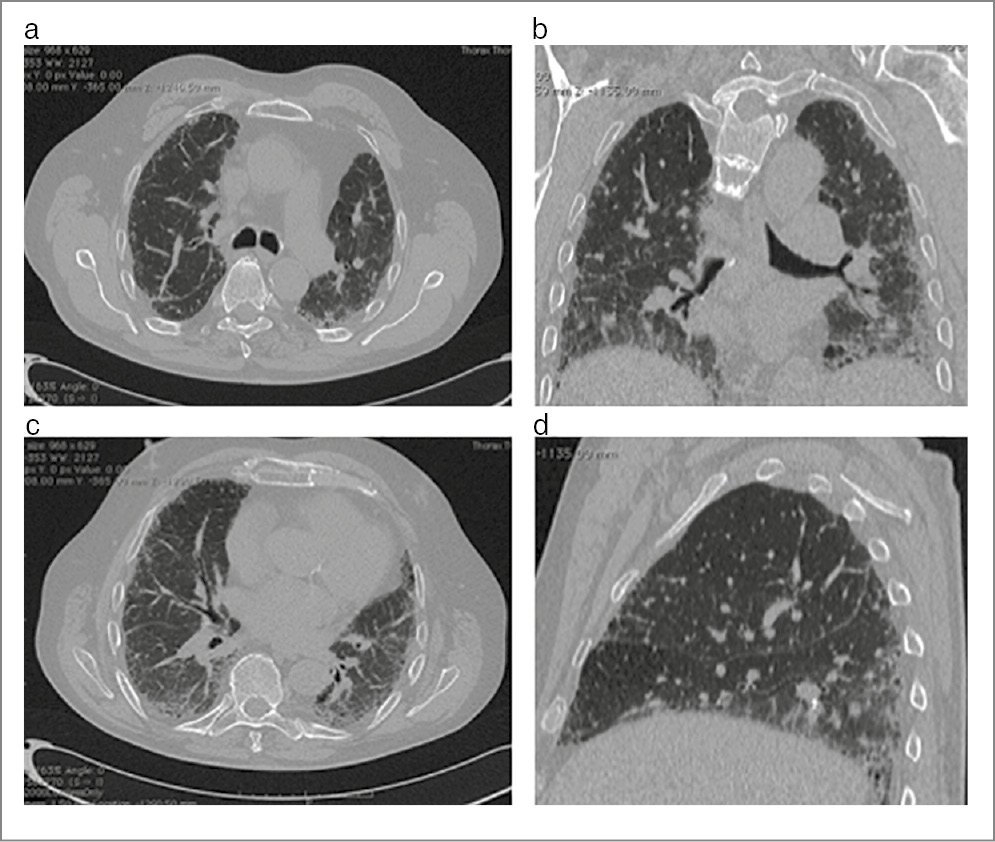

КТ ОГК (рис. 24): КТ-паттерн вероятной ОИП, отрицательная динамика в виде увеличения количества тракционно расширенных бронхиолоэктазов.

Рис. 24. КТ ОГК пациента Х от 08.08.2020 в сравнении с КТ ОГК от 05.04.2023.

Контрольное обследование пациента через 3 года и 1 мес

Жалобы: нарастание симптомов, одышка беспокоит уже при обычном темпе ходьбы.

Аускультативная картина – прежняя. ЧДД – 20 в мин.

SpO2 в покое – 97% (ранее – 98%). ТШХ: десатурация – до 89% (ранее – 90%). Прошел 362 м (ранее – 380 м). ДН II степени.

КТ ОГК: КТ-паттерн вероятной ОИП, отмечается некоторая отрицательная динамика в виде нарастания ретикулярных изменений и увеличения количества тракционно расширенных бронхиолоэктазов.

Таким образом, автор делает вывод о том, что препарат пирфенидон обладает достаточным антифибротическим противовоспалительным действием у больных с ИЛФ. Особенностью данного случая является хорошая клиническая переносимость препарата, стабилизация патологического процесса в легких и некоторое улучшение тестов функции внешнего дыхания в течение 1-го года приема препарата.

Однако через 3 года отмечена тенденция к нарастанию фиброза по данным КТ и рестриктивных изменений по данным функциональных методов обследования, что свидетельствует о прогрессировании заболевания.